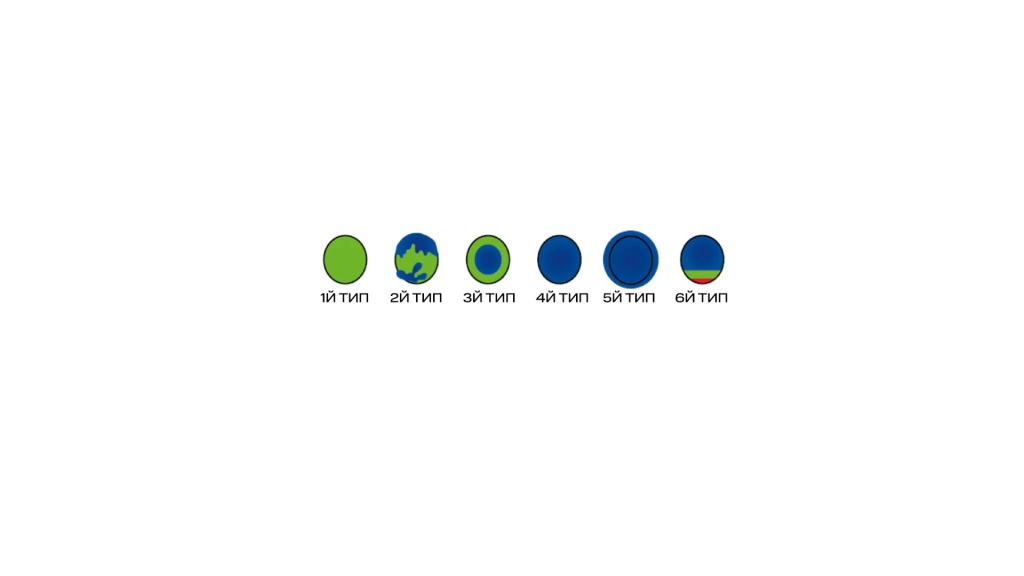

В 2005 году в университете Цукуба была предложена шкала эластотипов, ее также называют шкалой Уено (по автору). По данной шкале выделяется 5 эластотипов, и отдельно 6 эластотип – BGR-артефакт, характерный для жидкостного компонента. 1–2 и BGR типы, как правило, характерны для доброкачественных образований, 4–5 – для злокачественных.